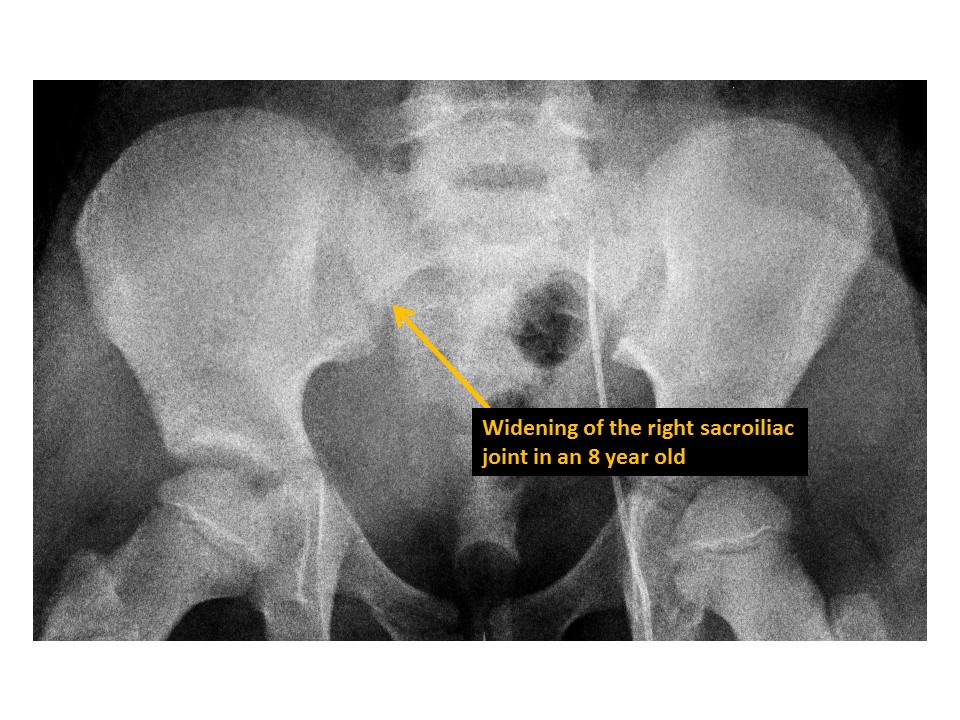

The sacroiliac joints are widened and asymmetric. [Yes/No]

There is malalignment at the inferior margin of the sacroiliac joints. [Yes/No]